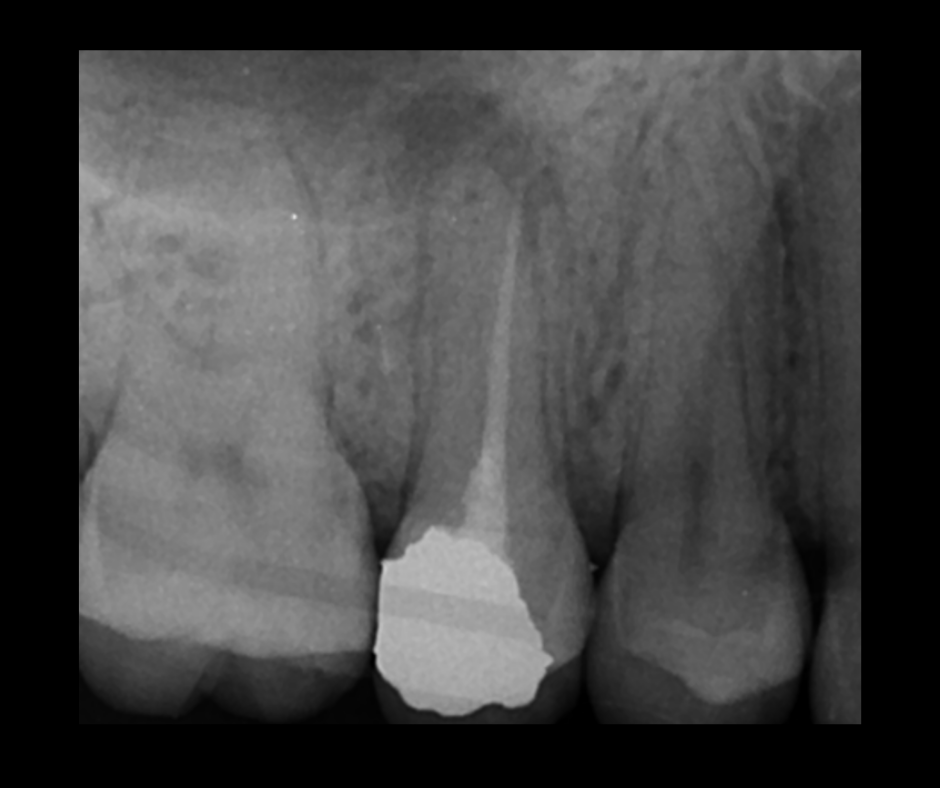

This course focuses on modern single-file endodontic systems, guiding participants through diagnosis, case assessment, access cavity design, canal location, root canal system preparation, and obturation techniques.

• To re-examine access cavity design and its importance in endodontic success

• To gain confidence in endodontic obturation and develop an understanding of various obturation techniques and methods of developing predictable, reproducible endodontic obturation

16.20 – 18.00 – Obturation and Orifice seal